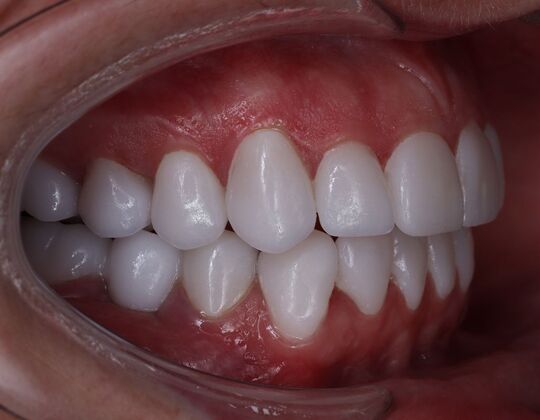

Porcelain Veneers: Michelle

Description

A smile is a very important part of one's appearance and is often the first thing people notice. Every person has a different color of teeth, and many have a different shape. Luckily there is a solution to improve your smile: Veneers!